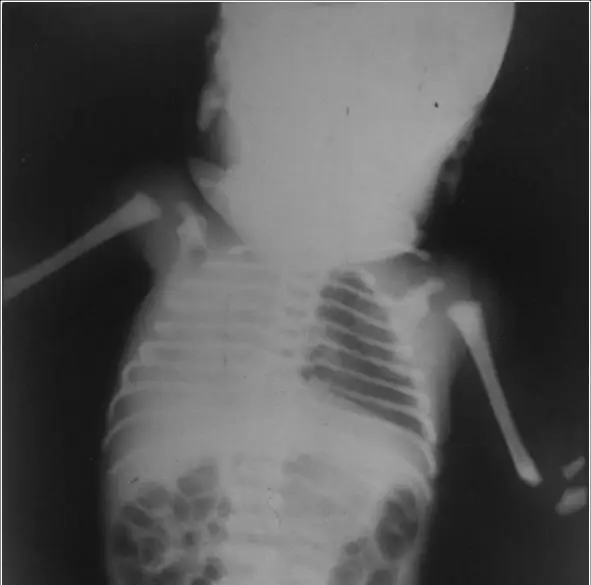

本張 X 光為嬰幼兒胸部正面 X 光(AP view)。影像重點如下:

- 右側半胸完全白化(complete right-sided white-out / opacification):右側胸腔呈現一片均質白色,無可辨識的肺紋路或支氣管充氣影(air bronchogram)。

- 縱膈與氣管向右偏移(ipsilateral mediastinal shift):心臟及縱膈結構明顯偏向右側(即病灶側),此為關鍵影像徵象。

- 左肺代償性過度充氣(compensatory hyperinflation):左肺肺紋路往右側延伸,顯示左肺代償性擴張。

- 右側肋間隙縮小:支持右側胸腔容積減少。

結論:縱膈向右(病灶同側)偏移,代表右側肺組織有體積喪失(volume loss),而非有空間佔據性病變(space-occupying lesion)。